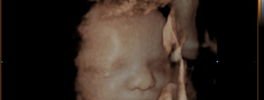

4D Foetal Face

4D Sonography -Foetal Face